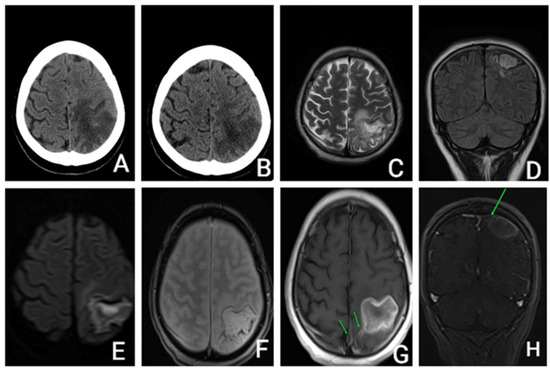

She underwent an unenhanced cerebral CT that revealed a parietal hypodensity with hemorrhagic transformation. (Figure 1).

The head CT scan, performed 9 days after admission, showed that the hemorrhage was in a resorptive stage. The diagnosis of CVT was then considered and contrast-enhanced cerebral MRI confirmed sagittal venous sinus thrombosis.

Close monitoring was performed after discharge, clinically, biologically, and radiologically. Three months after the CVT, she had completely recovered all her motor functions with the use of neurorehabilitation therapy. However, she developed symptoms of depression, for which she started receiving antidepressant medication. The brain MRI (Figure 3) showed the lesion as being chronic with the hemorrhage partially resolved at three months, with an aspect of organizing hematoma.

Three years later, she underwent another brain MRI (Figure 3) that showed a chronic ischemic left parietal lesion with partial peripheral gliosis and peripheral hemosiderin deposits.

Figure 1. (A,B)—Unenhanced CT axial: (A)—acute parietal stroke with hemorrhagic transformation; (B)—9 days apart—Unenhanced head CT axial: subacute parietal stroke with hemorrhage resorption. (CH): Brain MRI with and without contrast enhancement: (C)—T2 axial, (D)—FLAIR coronal, (E)—DWI axial, (F)—T2* hemo axial, (G)—T1 axial after i.v. contrast, (H)—T1 coronal after i.v. contrast. Ischemic area with hemorrhage transformation, hemosiderinic deposits mostly in periphery, central restricted diffusion and peripheral enhancement, filling defects of the sagittal venous sinus and of a cortical vein towards the affected left parietal area. CT—computer tomography; T1—weighed image; T2 weighted image; FLAIR—fluid attenuated inversion recovery; DWI—diffusion weighted imaging; T2* hemo—T2 weighted sequence.